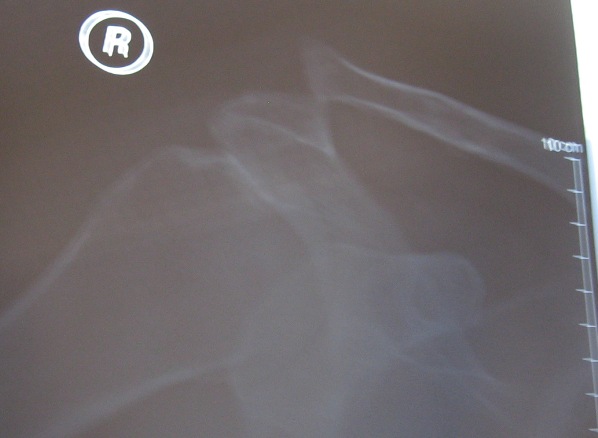

Dad's just had his rumble in the jungle. I'll let him post something about it when he feels like it, but suffice to say that 6 broken ribs and a displaced AC joint later, he's probably thinking the ride out to Kingaroy with the boys could have turned out a little better....

Sheeeeeet! Wo. I have had the same AC injury so I'll give your dad some tips to speedy recovery! Ya two just got to get back into cars....

How come your Dad copywrited his xray?

Get better soon!

It's actually not a bad plum colour...it would make a good Cobra Paint Job!

Dad's bruise has grown heaps since that photo, but believe me Warren, it's no longer the nice plum colour that you'd want to paint a Cobra.......